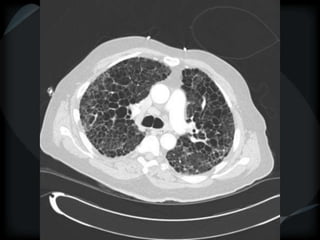

CT features of tuberculosis

 Transbronchial spread – tree-in-bud

 Transbronchial and hematogenous

Tuberculosis

bronchiolitis + hematogenous

TB bronchiolitis + hematogenous